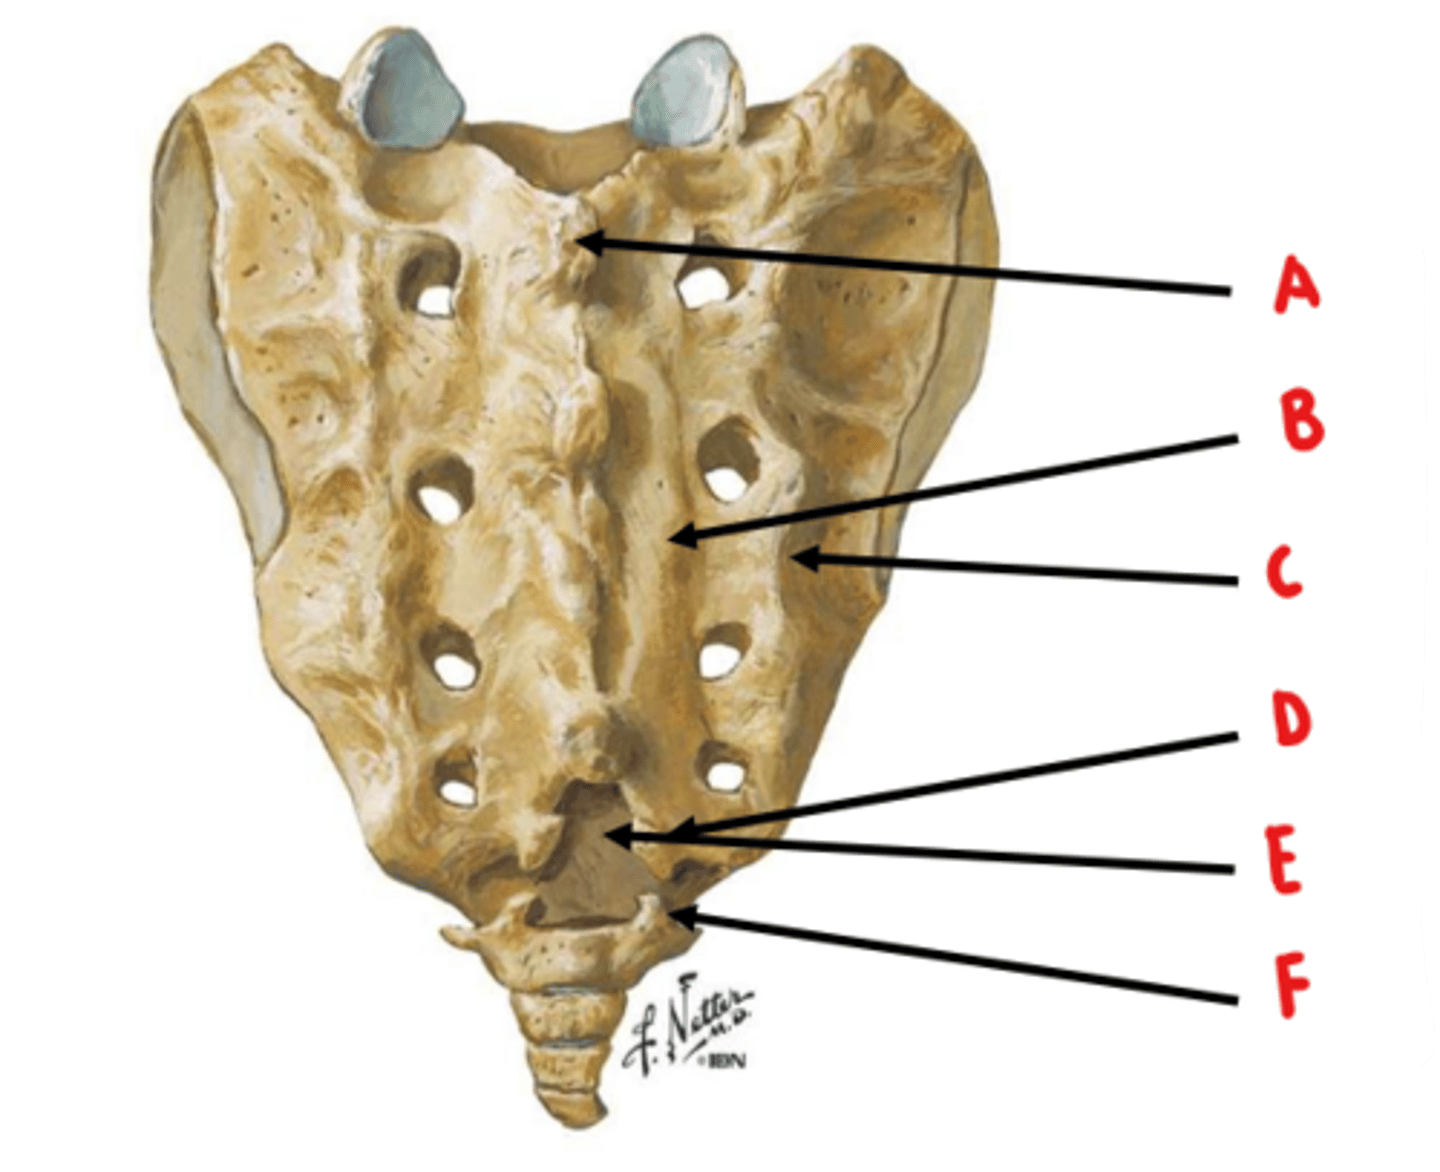

median sacral crest

Identify A

medial sacral crest

Identify B

lateral sacral crest

Identify C

sacral cornua

Identify D

sacral hiatus

Identify E

coccygeal cornua

Identify F

anterior sacral foramen = ventral rami

posterior sacral foramen = dorsal rami

ventral rami are larger because they innervate a larger area of tissue

What structures exit through the anterior and posterior sacral foramen? Which is larger and why?